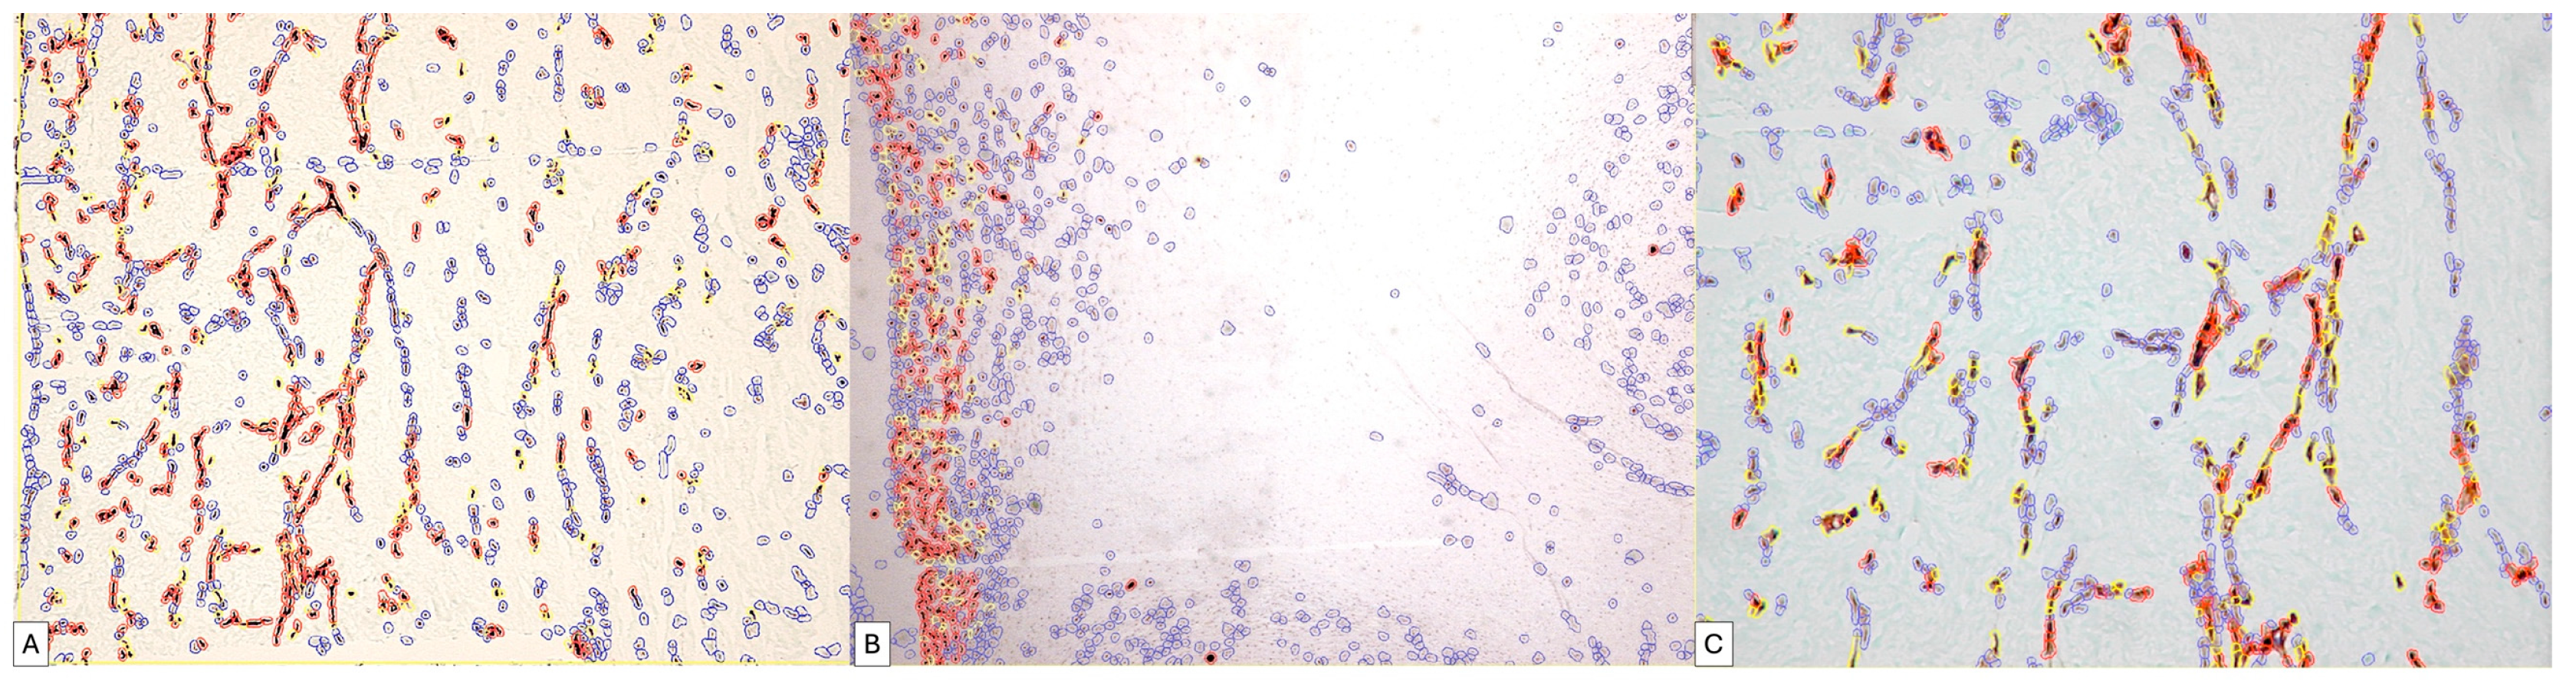

Regarding the immunohistochemical expression of podoplanin in the umbilical cord, the digital image analysis detected a very high variability between the number of positive cells within the umbilical cord; thus, at the periphery of the umbilical cord, we detected a total of 1500 positive cells corresponding to an approximate area of 1857501px until, in the center, we detected a total of 223 cells on a similar microscopic area, about seven times smaller between the periphery of the umbilical cord and mucous connective tissue. Virtually all umbilical cord specimens showed an IHC+ reaction to podoplanin, but the intensity of the expression was different. The quantification of the ALLRED score combining the cell proportion and intensity of expression demonstrated that 88.9% of all evaluated specimens had an Allred score of seven and eight, which supports an intense expression of podoplanin in the umbilical cord and placentas at term.

Of these cases, 73.3% presented an ALLRED score of seven, the rest being represented by the expression of a maximum ALLRED score of eight (Figure 7).

The positivity percentage of the umbilical cord cells was extremely variable such that from a total number of cells of a specimen, a positive percentage ranging from 3.65% in the center of the umbilical cord to 81.37% at the periphery could be detected in the umbilical cord. A percentage of approximately 61% of the analyzed specimens showed a percentage of positive cells above 80% of the total number of positive cells.

Regarding the histological score (H-Score), in 83.3% of cases, it had a value above 100 (Figure 8A,B).

Similar results were recorded in the assessment of placental villi, where we also recorded a variability in the Allred score.

Figure 7. Digital image analysis of umbilical cord specimens immunohistochemically stained with PDPN. Cells with increased intensity are marked with red, those with medium intensity are marked with orange, weakly positive ones are marked with yellow and negative cells are annotated with blue automatically by the image analysis system. Note the increased density of red signals at the periphery of the umbilical cord (B). The variability in the expression is dependent on the area of the umbilical cord, progressively decreasing in the middle area of the umbilical cord (A) and in its central area (C).